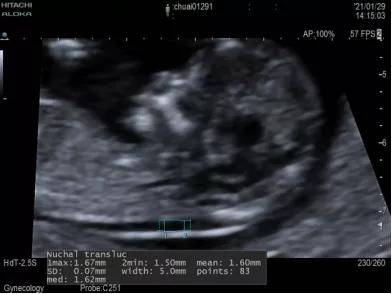

孕3个月的时候,孕妈们会做一项NT检查。超声医生在给做完NT检查后,经常会被问到“NT是什么?”,“NT检查是查什么的?”等问题。对此,北京儿童医院顺义妇儿医院超声科啜永林医生就来给孕妈们普及一下NT检查的一些相关内容。

NT即颈项透明层(nuchai translucency),是指早期妊娠胎儿颈背部皮下液体积聚的厚度。正常胎儿淋巴系统建立之前,少量淋巴液聚集在颈部淋巴管内,形成NT。14周后胎儿淋巴系统发育完善,聚集的淋巴液迅速引流到颈内静脉,NT通常会消退。早期妊娠胎儿颈背部皮下液体的增多和染色体异常相关性,使测量NT厚度成为超声筛查非整倍体的方法。

NT检查方法?

采用高级彩色超声扫描仪测量颈背部皮下液体积聚的厚度。必须同时满足以下条件才能测量此值。

1.胎儿头臀长为45-84mm之间。

2.颈部在自然姿势下取正中失状切面。

3.将头部及上胸部图像尽可能放大。

4.在透明层最宽处测量厚度。

5.至少测量三次,并记录最大值。

NT测值多少为异常?

NT测值通常随孕周的增大而增加,NT厚度超过第95百分位(相当于2.5mm)可认为NT增厚;NT厚度超过3.0mm则公认为NT增厚。多种文献报道,NT厚度>3mm时,90%为正常胎儿,10%为异常胎儿;NT厚度>6mm时,90%为异常胎儿。